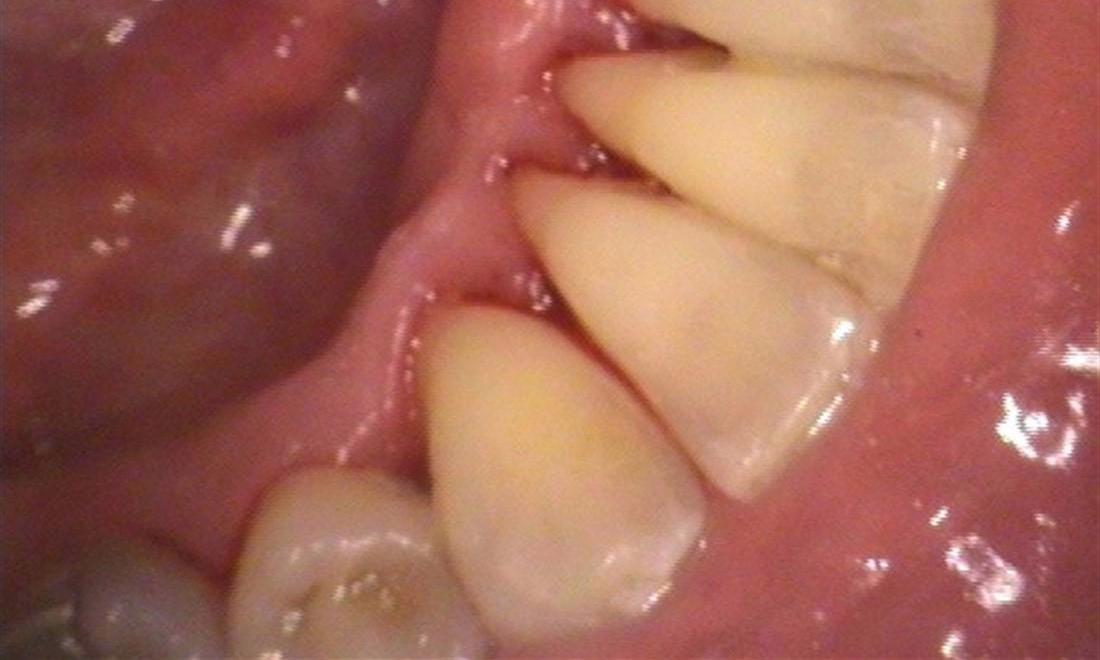

Calculus Removal in Allentown PA

This dental patient arrived at our Allentown dental office with heavy calculus also known as tartar. Calculus compromises health of gums and can potentially lead to periodontal disease, better known as gum disease. The tartar was removed during a professional teeth cleaning provided by our dental team.